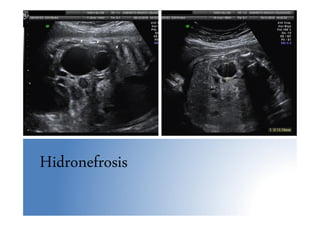

• Hidronefrosis: > 10 mm. 4 grados. Imágenes eco(-)

Hidronefrosis

Anomalías nefrourológicas • Uropatíasobstructivas – Son el 75% de las anomalías nefrourológicas Dx prenatalmente – Más frecuente en varones 5:1 – Tasa de resolución espontánea elevada (40%) – La más frecuente la dilatación ureteropiélica • Ectasia piélica: >7mm en 3º T. Control eco sem. 36-37 • Hidronefrosis: > 10 mm. 4 grados. Imágenes eco(-) comunicadas entre sí, parénquima renal conservado o adelgazado, controles eco/4-6 sem., 80% manejo postnatal expectante • Doble sistema pielocalicial: aislado es una variante de la normalidad, muy frecuente, 2 pelvis separadas no comunicadas con duplicación parcial o completa de uréteres. Ureterocele frecuente